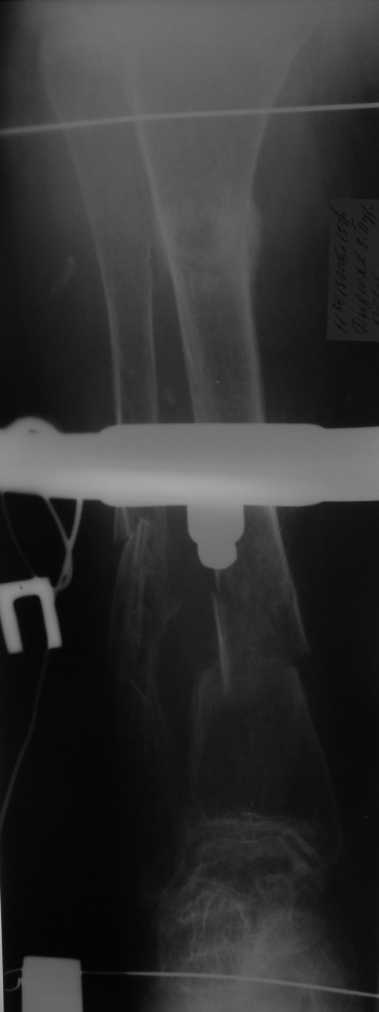

Но даже при малоинвазивной методике лечения применимой для даной больной существуют следующие проблемы: выраженный остеопороз, тонкий кортикал, очень широкий канал.

Контрольные рентгенограммы прилагаю.

Проблема в том, что в сагитальной плоскости угол голеней =30 градусам. Ширина канала 30.

Будет ли остеосинтез стержнем стабильный?